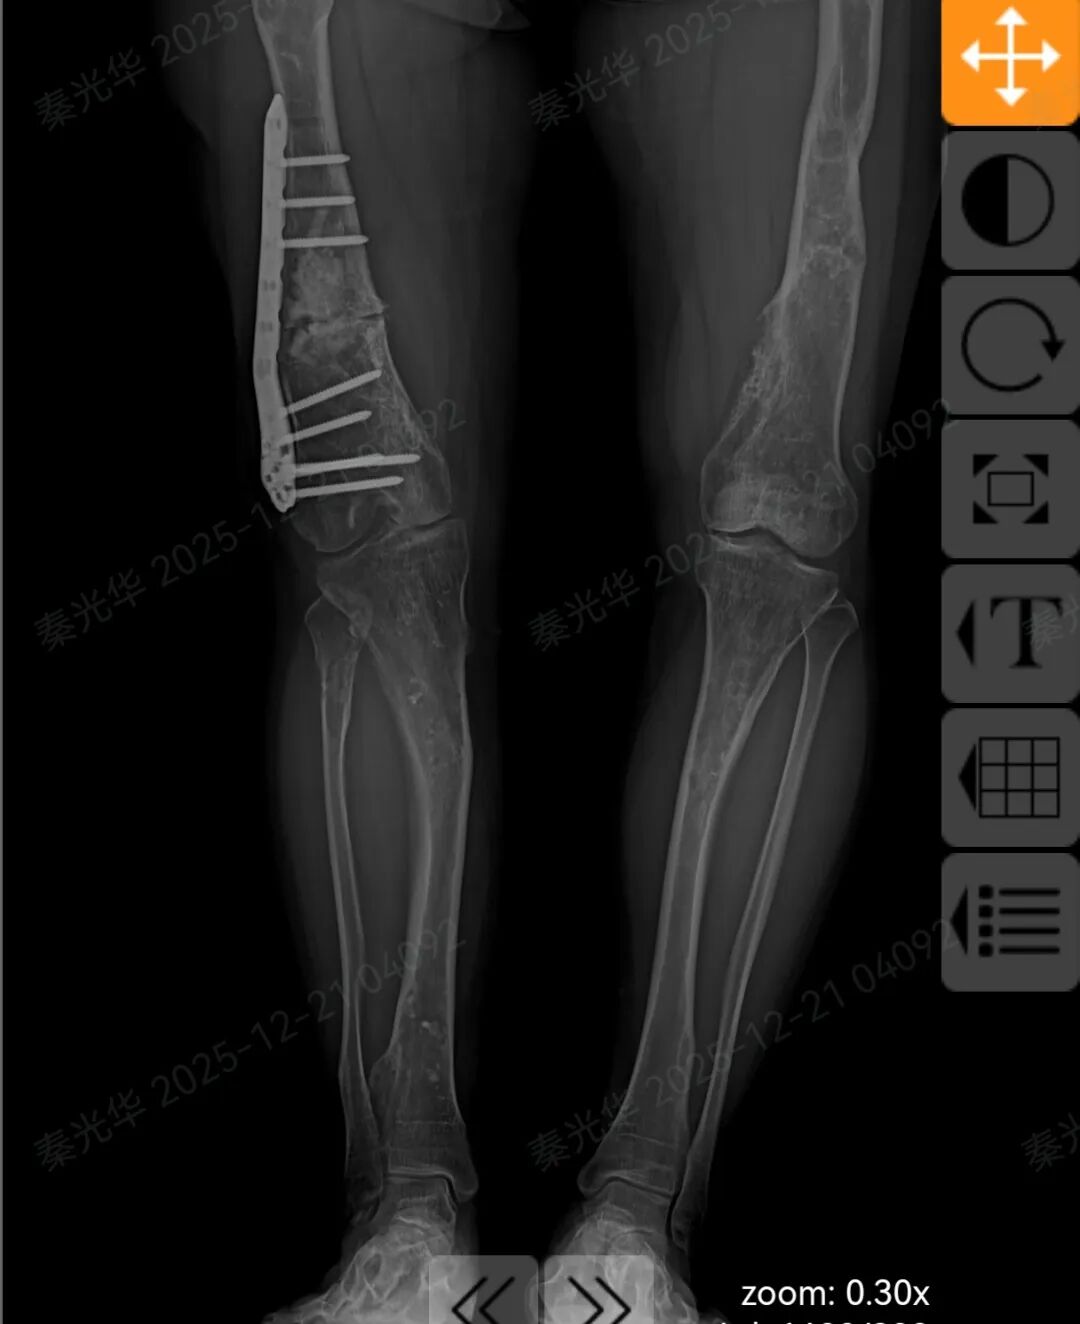

患者术后核磁显示

术后患者右侧股骨形态恢复正常,双下肢成功等长!

患者术后核磁显示双下肢恢复等长